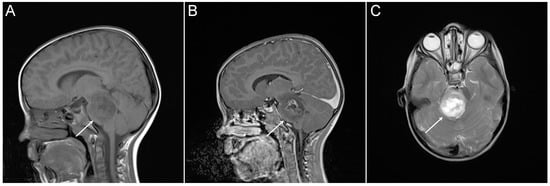

- Hankinson, T.C.; Campagna, E.J.; Foreman, N.K.; Handler, M.H. Interpretation of magnetic resonance images in diffuse intrinsic pontine glioma: A survey of pediatric neurosurgeons. J. Neurosurg. Pediatrics 2011, 8, 97–102. [Google Scholar] [CrossRef] [PubMed]